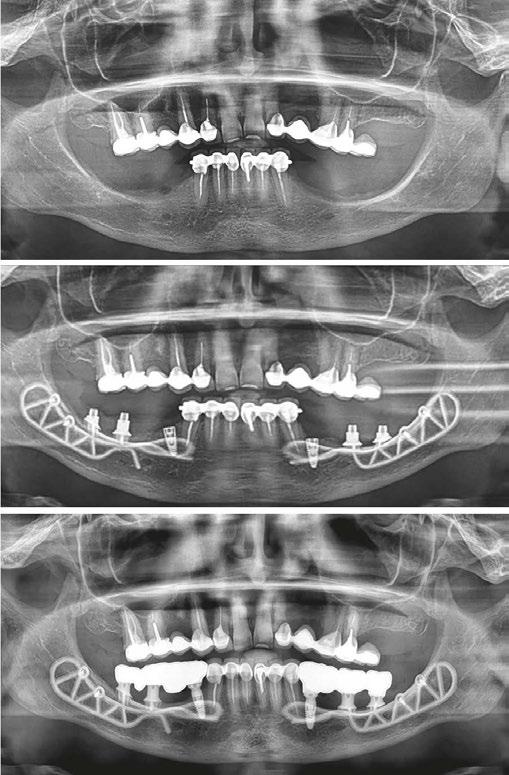

A 59-year-old male reported to the dental office with missing maxillary teeth due to poor oral hygiene. Treatment planning was done for All-on-4 implant placements followed by prosthesis. A complete medical history was obtained and was negative for any significant medical problems. The patient denied being allergic to any medication as well. The patient agreed to the implant placement and was advised to have an orthopantomogram (Figure 1).

On the day of the surgery, before commencing the procedure under strict asepsis, the patient was asked to rinse with 0.12% chlorhexidine gluconate mouthwash (Peridex™; 3M™). Local anesthesia with a vasoconstrictor was infiltrated buccally and palatally into the posterior and anterior maxilla on both the sides using S-blades (straight) (Zabby, India). The incision was made

on the crest of the ridge in the region of teeth Nos. 15-25. While creating the incision, bleeding was noticed in the region of tooth No. 15 which intensified during the flap reflection (Figure 2). Bleeding was pulsatile, indicating an arterial bleed. Initially attempts to control bleeding included a pressure pack and ice pack, and the bleeder was isolated and the vessel ligated (Figure 3). The bleeding could be controlled, and the procedure was completed by placing four Bioner implants (Bioner, Spain), size 4/10 mm. Sutures were placed, and patient was kept on basic medication for pain and infection control. Immediately after the surgery, the patient was advised to get a CBCT. As shown in Figure 4, a coronal view and Figure 4B (yellow arrows), the position of the artery can be seen.

In the follow-up sessions, the patient was comfortable, but did complain of mild swelling which subsided within 4-5 days. A post-op CBCT showed excellent recovery, bone width, and proper implant placement (Figure 5).

Figure 1: Pre-op panoramic radiograph

Figure 2 (left): Alveolar antral artery (AAA). Figure 3 (center): The artery has been ligated with suture. Figures 4A and 4B (right): CBCT post-implant placement and position of the artery coronally (top). 4B. Showing the position of alveolar antral artery (AAA) in relation to implant placement as indicated by the yellow arrows (bottom)

Figure 5: Panoramic radiograph following implant placement